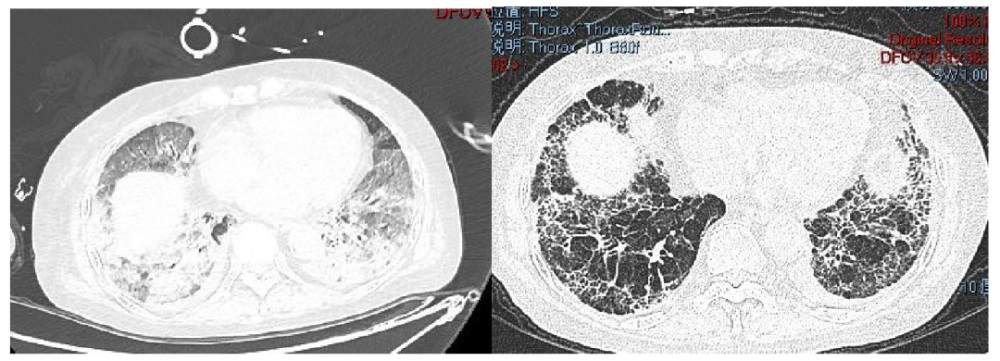

肺纖維化高發(fā)

《Nature Medicine》2021年發(fā)表了“Post-acute COVID-19 syndrome”,研究指出呼吸困難在60-100天的隨訪期內(nèi)的發(fā)生率為42%-66%,有6.6%的患者因持續(xù)低氧血癥需要補充氧氣?;颊叱鲈汉?個月評估發(fā)現(xiàn)約25%的輕度至中度病例存在纖維化,在重癥病例居多的隊列中,約65%的康復(fù)者存在肺纖維化。